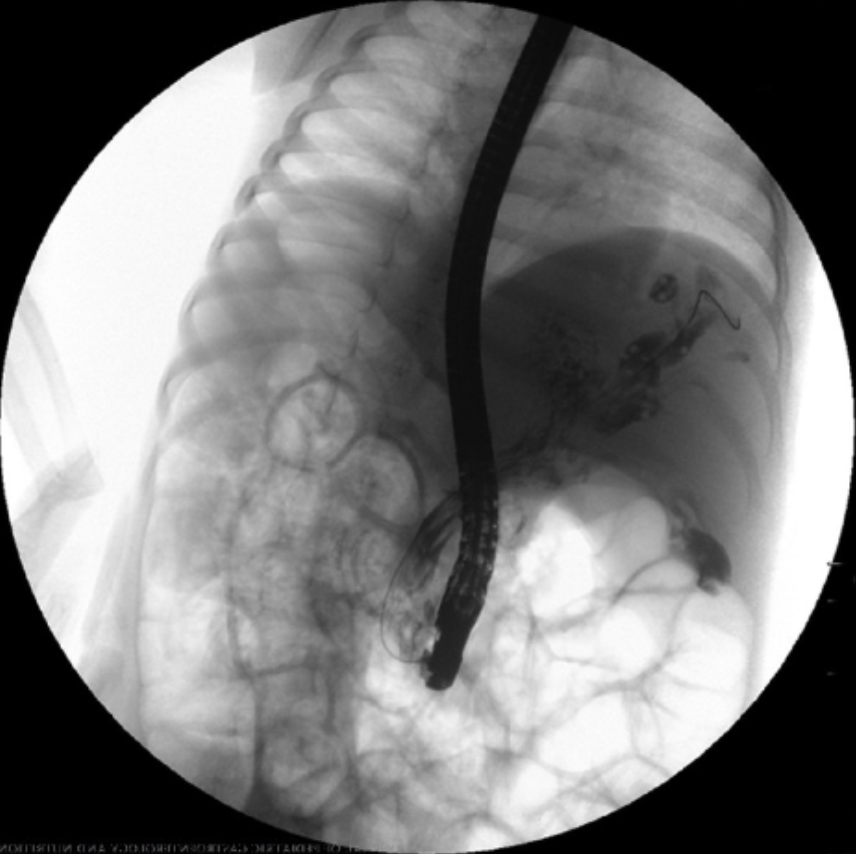

3 yo boy with abd pain and fever for the last 10 days. Abd US shows a dilated CBD and echogenic content. Side viewing endoscopy and cholangiography as shown. What is the next step in management? Answer and learn more 👉 bit.ly/3htf9YP?utm_so… #imageofthemonth #quickpoll

JPGNonline's tweet image. 3 yo boy with abd pain and fever for the last 10 days.  Abd US shows a dilated CBD and echogenic content. Side viewing endoscopy and cholangiography as shown.

What is the next step in management?